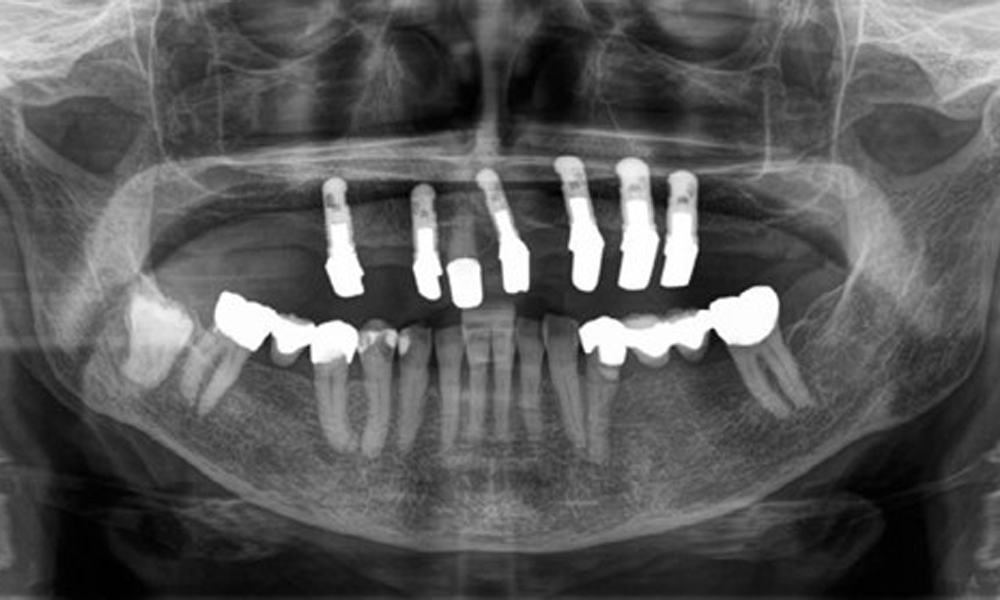

Aus dem radiologischen Befund zeigt sich ein teilbezahntes Gebiss mit Implantaten im Oberkiefer an 15, 13, 21, 23, 24, 25 und einer Teleskopkrone 11. Im Unterkiefer sind suffiziente Brücken von 37–34 und 45–47 vorhanden. 48 ist retiniert. 43 distal besteht der Verdacht auf Sekundärkaries und 44 mesial Verdacht auf Sekundärkaries. 44 ist mit einer nicht röntgenopaken Unterfüllung versorgt.

Es zeigt sich ein generalisierter horizontaler Knochenabbau von ca. 10–30 % und lokalisiertem vertikalen Knochenverlust an 22 und 42. (Abb. 5)

Panoramaschichtaufnahme. Es zeigt sich ein generalisierter Knochenabbau zwischen 10-30%. 44 und 43 haben einen radiologischen Verdacht auf eine Sekundärkaries.

Abb. 5: Panoramaschichtaufnahme. Es zeigt sich ein generalisierter Knochenabbau zwischen 10–30 %. 44 und 43 haben einen radiologischen Verdacht auf eine Sekundärkaries.